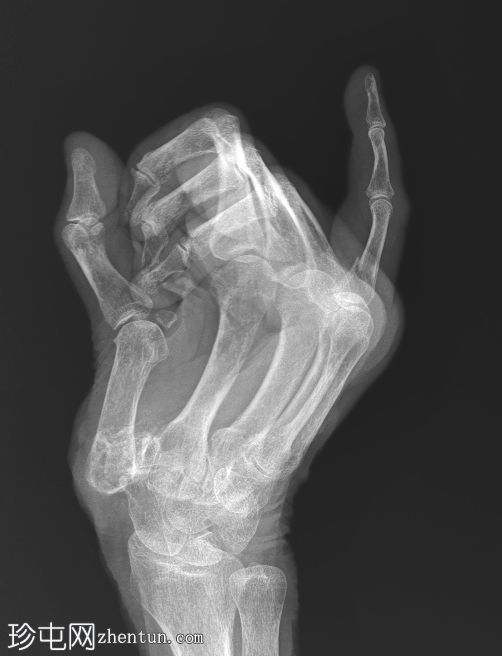

右手X线片

X线片

正位

斜位

小指近节指骨干轻微移位螺旋形骨折,周围软组织肿胀。怀疑拇指掌骨基底部和大多角骨骨折。

第一腕掌关节脱位,周围软组织肿胀。

第二至第五腕掌关节正常。桡腕关节、掌指关节和指间关节正常。尺骨茎突正常。

骨密度降低。